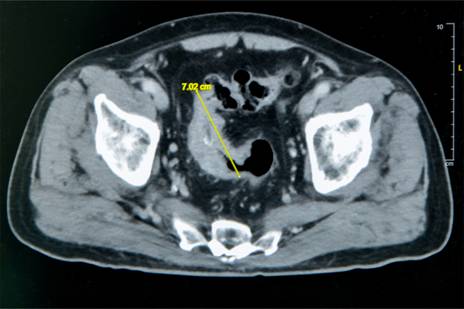

大腸直腸外科主任張譽耀醫師表示,老翁罹患乙狀結腸癌,腫瘤約7公分造成腸子幾乎完全阻塞,也導致老翁一進食就會肚子又脹又痛;術前因為不敢進食,老翁體重下降、營養不足,也可能造成傷口癒合不良。老翁的手術其實會有兩個傷口,一個是肚子上的傷口、一個腸子的傷口,若腸子傷口癒合不良會造成腸吻合滲漏,到時就必須做人工肛門了!所幸經過提早住院,透過靜脈營養針先建立營養,讓病人強健身體後才手術,術後傷口果然順利癒合。手術順利完成,老翁術後恢復良好,疼痛程度遠低於預期,他開心表示:「沒想到這麼快就能下床,真的很感謝醫師。」

圖1:老翁罹患乙狀結腸癌,腫瘤約7公分造成腸子幾乎完全阻塞。